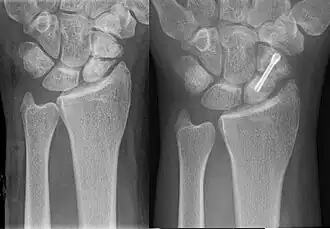

| An X-ray showing a fracture through the waist of the scaphoid | |

-

A subtle scaphoid fracture -

A more obvious scaphoid fracture on a scaphoid view X ray -

Radiolucency around a 12 days old scaphoid fracture that was initially barely visible.[13]